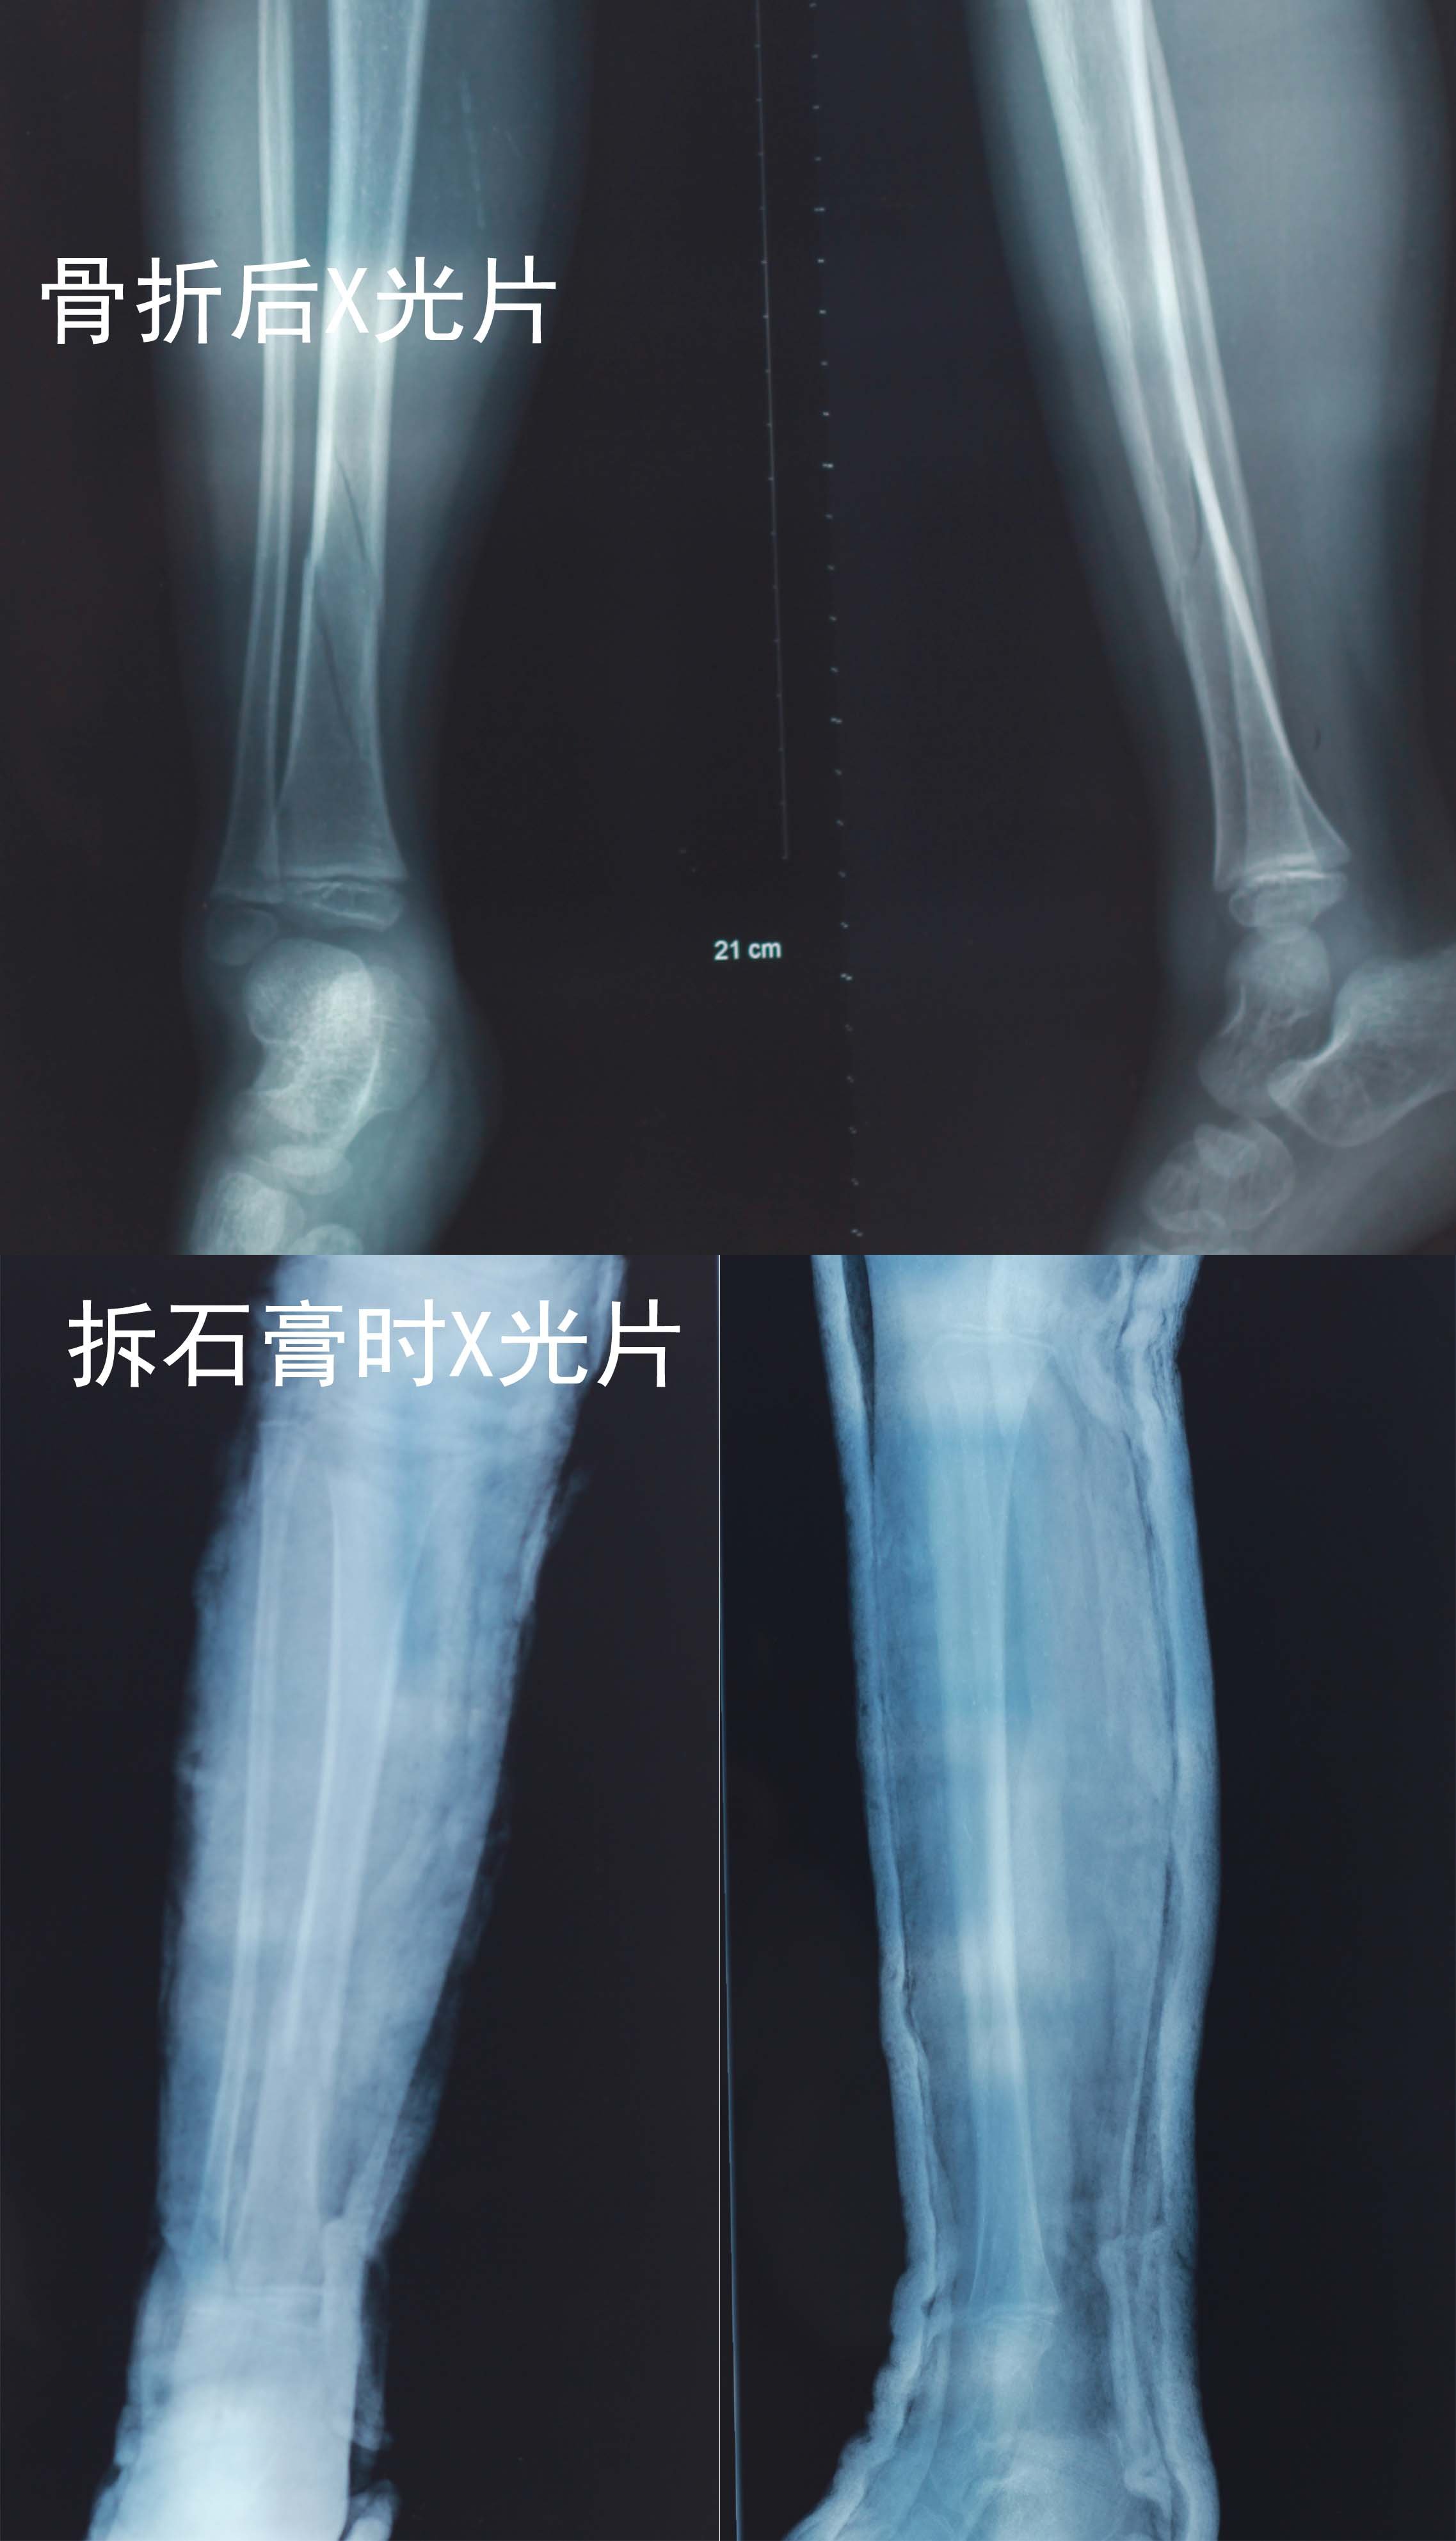

患者信息:男 5岁 病情描述(发病时间、主要症状等):今年,5周岁孩子右腿胫骨扭曲性骨折,8周后拆石膏。拆石膏4周后,走路看得出还有点瘸,跑的话,就更严重。去医院看过,医生说没有什么问题,不需要特别注意什么,慢慢会好的。但是看他走路这样,我们家长心里很着急。想得到怎样的帮助:请问孩子是否能完全恢复,是否需要恢复训练?如何训练?曾经治疗情况及是否有过敏、遗传病史:无